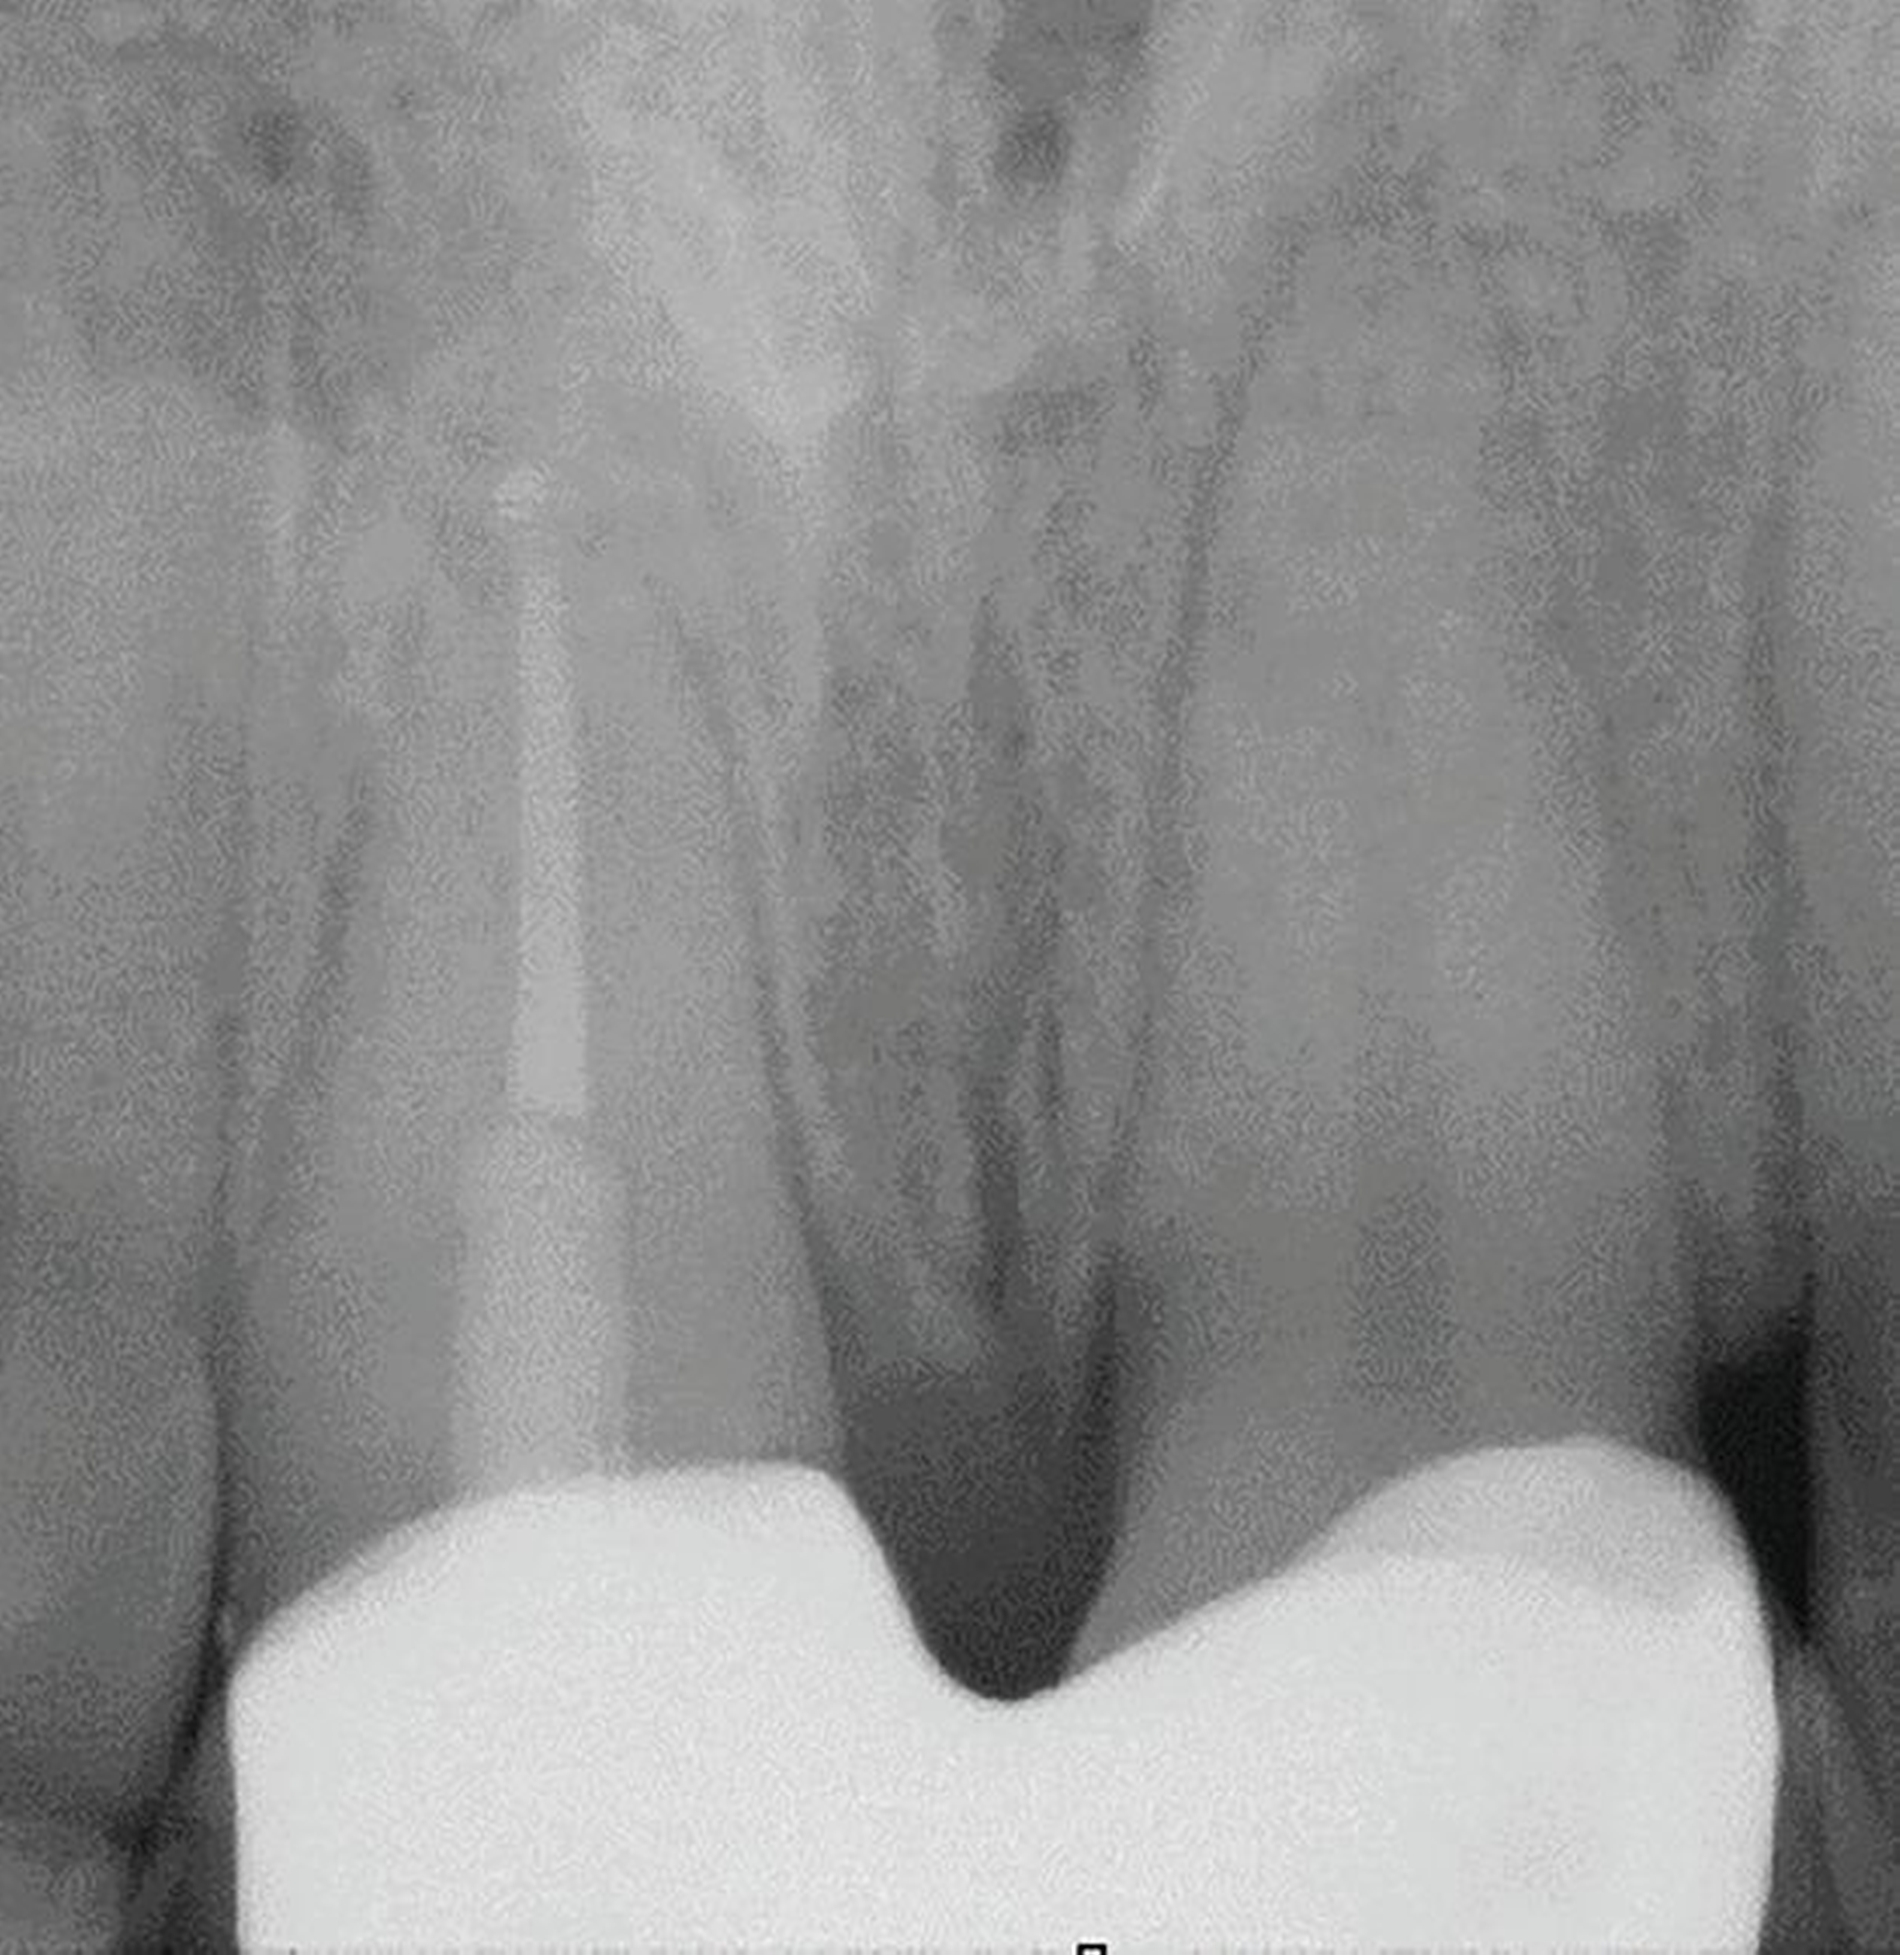

Anhand der von uns durchgeführten Einzelzahnaufnahme konnte die alio loco gestellte Erstdiagnose korrigiert werden: Wurzelfraktur des Zahnes 22 mit Kommunikation zur Mundhöhle (Abbildung 19). Der Patient favorisierte nach Diagnosesicherung zunächst Zahnersatz an 22 durch ein Sofortimplantat, weshalb eine DVT-Aufnahme zur weiteren Planung angefertigt wurde (Abbildung 20). In der Aufnahme zeigte sich jedoch, dass keine suffiziente vestibuläre Knochenlamelle vorhanden und somit der Erfolg eines Sofortimplantats nicht sicher vorhersagbar war. Nach umfassender Aufklärung entschied sich der Patient für den Zahnerhalt und eine Extrusion mit Magneten (Abbildungen 21 bis 24).